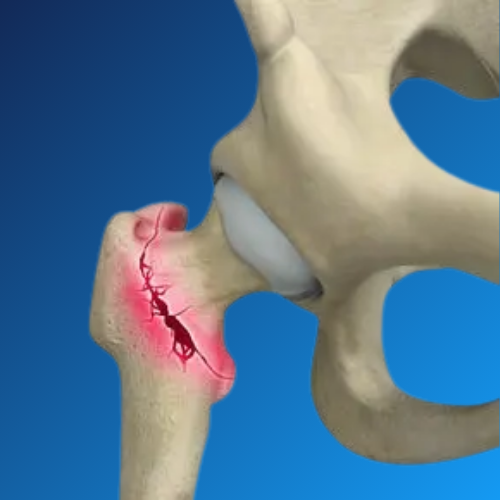

Hip Fracture Care focuses on the prompt and effective treatment of broken hip bones, typically occurring due to falls, accidents, or weakened bones from osteoporosis. Dr. Nishant Bhatia offers advanced surgical care for hip fractures, ensuring rapid pain relief, restored mobility, and prevention of complications.

Hip fractures are especially common among the elderly and require immediate medical attention. Delay in treatment can lead to serious issues such as blood clots, infections, or long-term disability.

Using state-of-the-art techniques and precision surgery, Dr. Bhatia ensures minimal tissue damage, faster healing, and safe outcomes for all age groups. His approach is tailored to each patient’s bone health, age, and activity level.